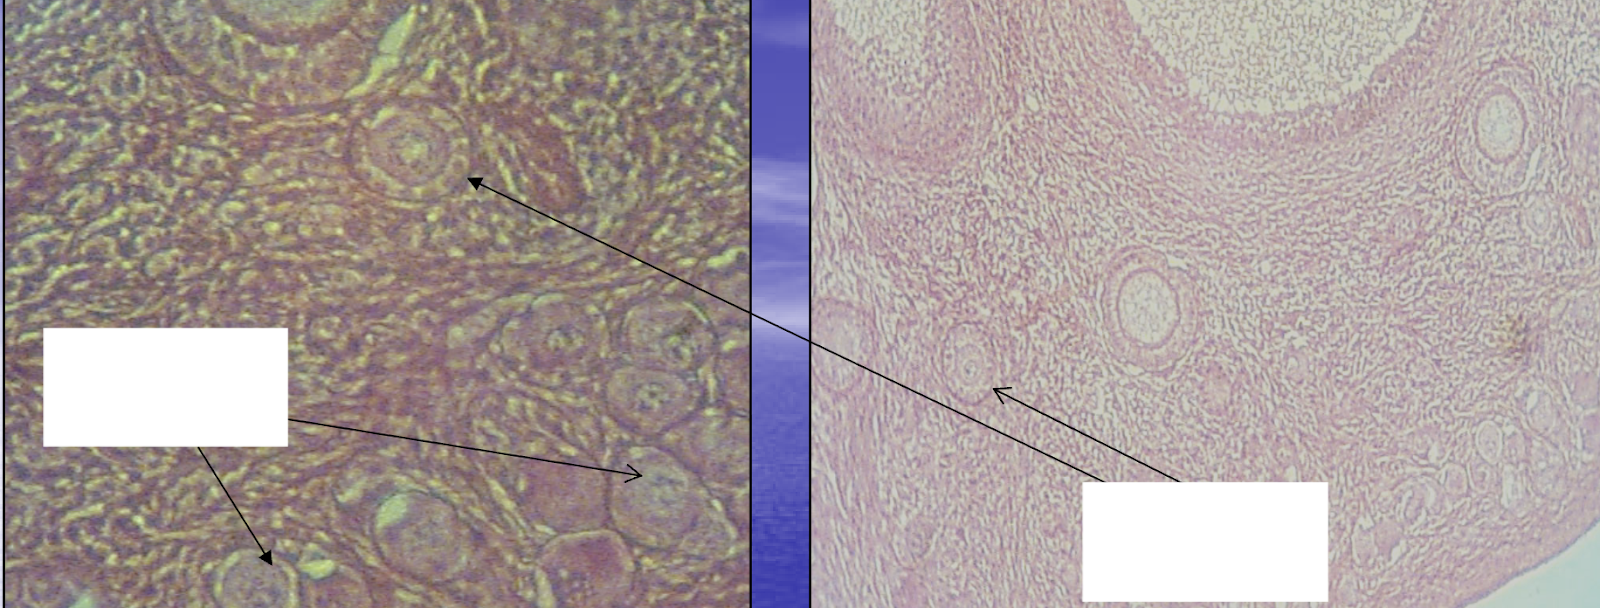

What structure is being indicated by the white box?

Follicular antrum

What structure is being indicated by arrow #1?

Stratum granulosa

What structure is being indicated by arrow #2?

Basal lamina

What structure is being indicated by arrow #3?

Theca interna

What structure is being indicated by arrow #4?

Theca externa

What structure is being indicated by arrow #5?

Tunica albuginea

What structure is being indicated by arrow #6?

Germinal epithelium